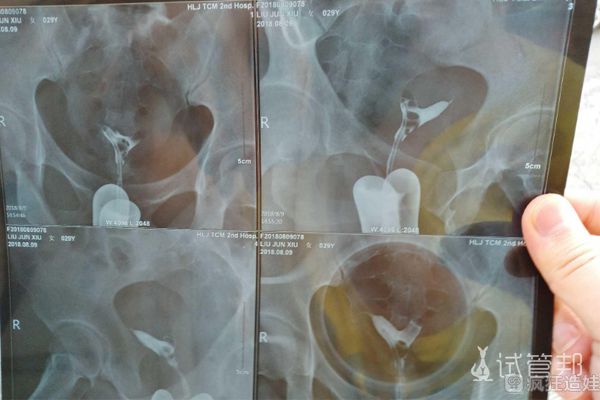

两年前结的婚,家里老人说,趁他们还能帮忙带,让我快要小孩,开始试着怀孕,结果试了半年没反应,大姨妈每次按时到,老公二姐劝我们去医院检查。做了一大推的项目,查出霉..